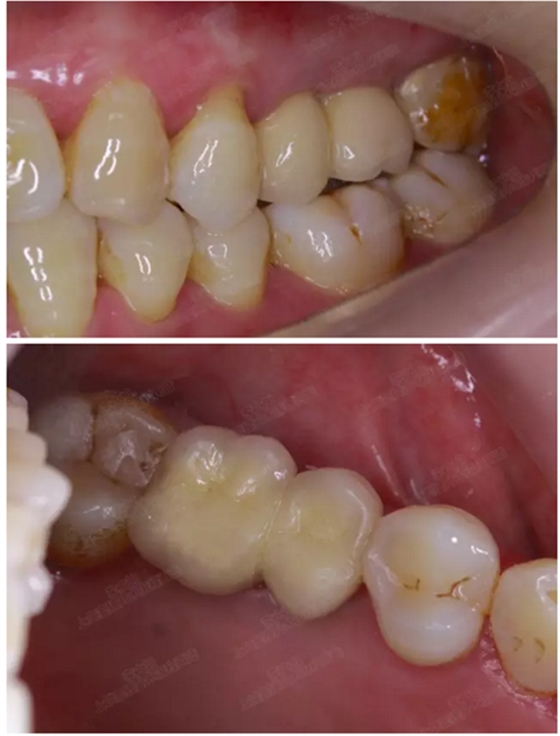

病例一

上頜竇多分隔3mm

05.png

提升8mm

06.png

07.png

修復時根尖片

08.png

09.png

口內(nèi)照片

001.png

修復后一年

002.png